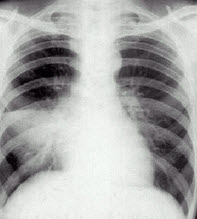

男性,59岁,高热、咳嗽、胸闷二天。诊断()

A:右中叶肺癌

B:右中叶肺不张

C:右中叶肺炎

D:右下胸膜肥厚

E:气胸